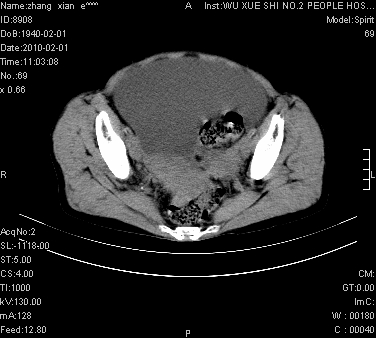

标题: CT24434:70岁 女 腹胀,腹水原因待查 [打印本页]

标题: CT24434:70岁 女 腹胀,腹水原因待查

大量腹水,脾脏囊性占位,子宫颈占位,右侧腹股沟淋巴结肿大,建议+c,先查妇科。

腹盆腔大量积液,子宫增大,子宫颈增大外形不规则,内见低密度影,膀胱后壁显示不清,右腹股沟肿大淋巴结,脾脏囊性占位,子宫颈占位,子宫颈癌?建议增强。

考虑:1、腹膜转移,大量腹水;

2、脾占位性病变;

3、左侧卵巢占位性病变,建议增强进一步检查。

考虑:1、腹膜转移,大量腹水;2、脾占位性病变;3、左侧卵巢占位性病变,建议增强进一步检查。支持